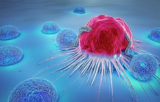

Cellule tumorali

Il cancro è una malattia caratterizzata dalla proliferazione incontrollata delle cellule, dovuta a mutazioni genetiche che interrompono il normale ciclo cellulare. A differenza delle cellule normali, le cellule cancerose perdono la capacità di rispondere ai segnali che regolano la crescita e la divisione cellulare e acquisiscono la capacità di dividersi indefinitamente. Queste cellule modificate si moltiplicano in modo incontrollato, formando tumori che possono invadere e distruggere i tessuti circostanti. Inoltre, le cellule tumorali possono staccarsi dal tumore originale e diffondersi in altre parti del corpo, un processo noto come metastasi. Le caratteristiche distintive delle cellule tumorali includono la capacità di sfuggire alla morte cellulare programmata e di indurre la formazione di nuovi vasi sanguigni per garantire l'apporto di ossigeno e nutrienti. Queste caratteristiche rendono il cancro una malattia complessa e multifattoriale, che richiede una comprensione approfondita dei suoi meccanismi per sviluppare strategie di trattamento efficaci. In breve, il cancro deriva dalla progressiva trasformazione di cellule normali in cellule cancerose, che perdono il controllo sulla crescita e sulla divisione e acquisiscono la capacità di metastatizzare, minacciando così la salute dell'organismo.